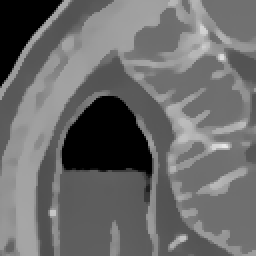

Elimination of noise in ultra low dose CT data

after strong smoothing